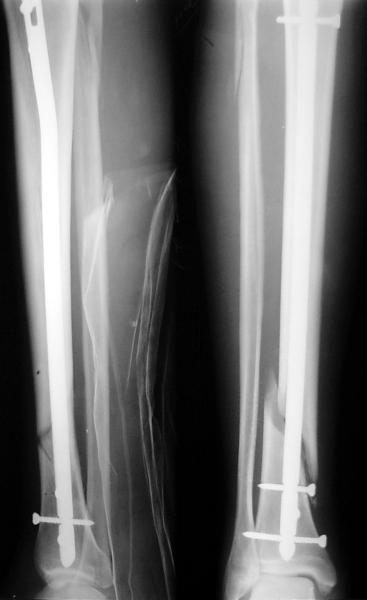

Как мне показать пример? Фото стоящего на одной оперированной конечности пациента? O! Пример, подвигнувший нас на некоторое изменение технологий. Пациент этот ходил с полной нагрузкой вопреки рекомендациям. В качестве подтверждения - сломанный проксимальный статический винт к 1 мес., а к 2 мес. - все остальные. Сейчас мы перешли на более fool-proof остесинтез.

На мой взгляд, на снимках, приведённых Вами - неправильно сростающийся перелом дистальной трети большеберцовой кости, состояние после остеосинтеза интрамедуллярным гвоздём.

Как Вы пишите снимок под номером 1 - менсяц после операции, под номером 2- два месяца после операции.

Вы не послали послеоперационный снимок, поэтому трудно судить о состоянии редукции после операции.

Установка с медиальной стороны гвоздя в области дистального фрагмента дополнительного шурупа помогло бы Вам репонировать и удержать перелом в анатомическом положении, предотвратило варусную деформацию и смещение по ширине.

Пример, приведённый Вами в нашей дискуссии по времени нагрузки после остеосинтеза не совсем удачный... Ваш больной имеет счастье, что первым согнулся проксимальный замыкающий винт, а не дистальный и гвоздь не пенетрировал голеностопный сустав.

I think that the X-Rays show S/P IMN of Spiral # of the Distal Tibia consoles in misalignment.

You wrote that a picture number 1 - f month after the surgery, and number 2-two months after the surgery.

You have not sent a postoperative X-Rays; so it's impossible to discuss about the condition of a reduction after operation.

Let to express concerning technique of operation my opinion... Insertion of a screw to medial side of a nail in distal fragment would help you to reduction and to keep this fracture in anatomic position has prevented varus deformity and displacement on width. By the way, if it is possible send a postoperative picture.